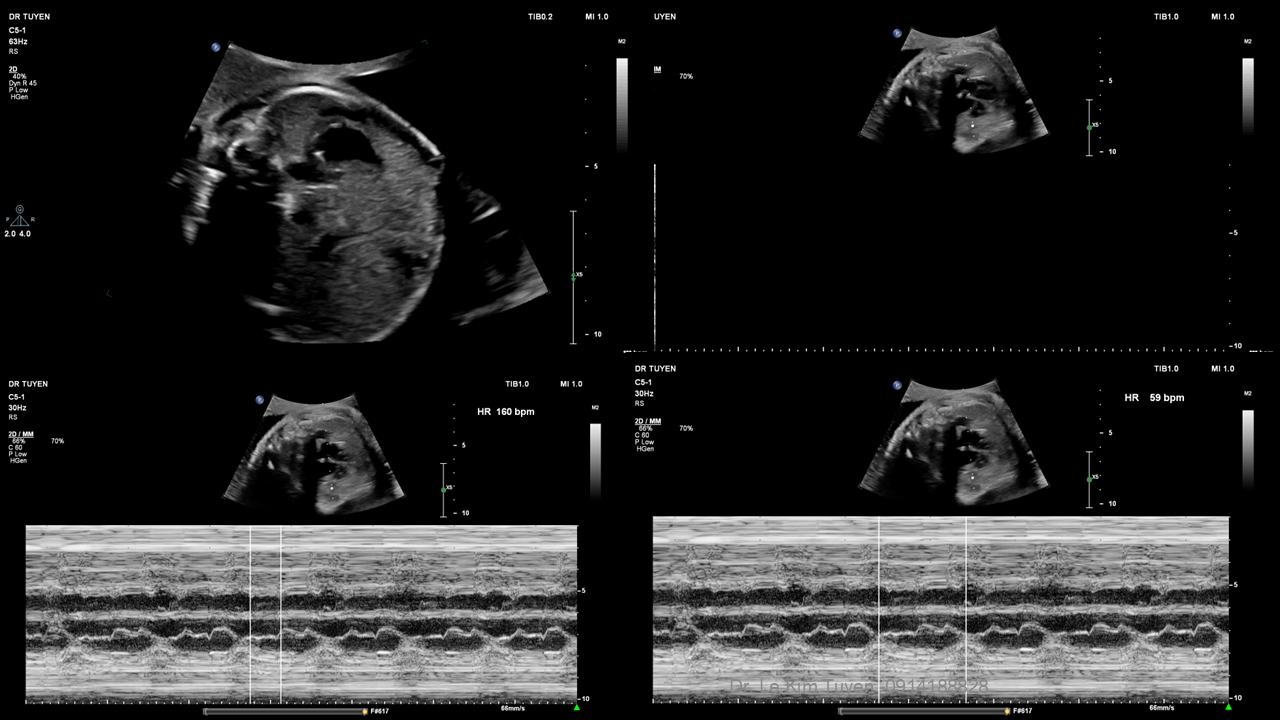

Áp dụng công nghệ Graphicflow trong phát hiện bệnh tim bẩm sinh cần cấp cứu sơ sinh

TS. BS. Lê Kim Tuyến

Bệnh viện Tim Tâm Đức